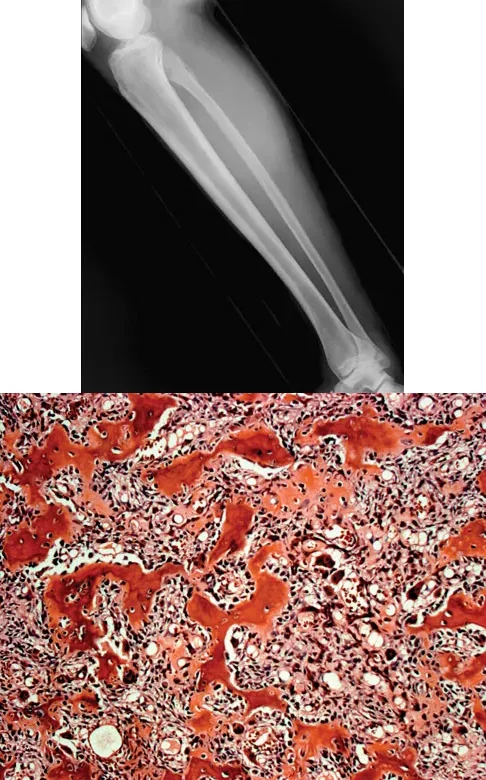

A 23-year-old man presents with right posterolateral knee pain, worse at night and relieved by NSAIDs. Imaging and histology are shown. The histologic specimen demonstrates a cellular, vascular stroma with plump osteoblasts producing immature woven bone. What is the currently preferred minimally invasive treatment for this lesion?

Explanation

Correct Answer: B

The clinical presentation, imaging (cortically based lytic lesion with surrounding sclerosis/edema), and histology (vascular stroma with osteoblasts and woven bone) are classic for an osteoid osteoma. Percutaneous radiofrequency ablation (RFA), typically under CT guidance, has become the preferred treatment method, offering high success rates with minimal morbidity compared to open surgical excision.

A 23-year-old man presents with right posterolateral knee pain that is worse at night and dramatically relieved by NSAIDs. Imaging reveals a well-circumscribed, cortically based lytic lesion in the proximal fibula with surrounding edema. Histology demonstrates a cellular stroma with plump osteoblasts producing immature woven bone. What is the preferred definitive treatment for this condition?

Correct Answer: Percutaneous radiofrequency ablation

The clinical presentation (night pain relieved by NSAIDs), radiographic appearance (cortically based lytic lesion with surrounding sclerosis/edema), and histology (plump osteoblasts producing woven bone in a vascular stroma) are classic for an osteoid osteoma. Percutaneous radiofrequency ablation (RFA), typically performed under CT guidance, has become the preferred, minimally invasive treatment of choice for most osteoid osteomas, offering high success rates and low morbidity compared to open surgical resection or curettage.

A 23-year-old man presents with right posterolateral knee pain that is worse at night and relieved by NSAIDs. Imaging and histology are provided. The histologic specimen is most likely to demonstrate which of the following?

Correct Answer: A cellular stroma with plump osteoblasts producing immature woven bone

The clinical presentation, imaging (cortically based lytic lesion with surrounding edema), and histology are diagnostic of an osteoid osteoma. Histologically, it consists of a highly vascularized nidus of interlacing trabeculae of osteoid and woven bone lined by plump, benign osteoblasts.

A 23-year-old man complains of right posterolateral knee pain that is worse at night and relieved by NSAIDs. Imaging and histology are shown. The histology demonstrates a cellular, vascular stroma with plump osteoblasts producing immature woven bone. What is the preferred modern treatment modality for this lesion?

The clinical presentation (night pain relieved by NSAIDs), radiographic appearance (cortically based lytic lesion with surrounding sclerosis), and histology (vascular stroma with osteoblasts and woven bone) are diagnostic of an osteoid osteoma. The preferred modern treatment for most osteoid osteomas is CT-guided percutaneous radiofrequency ablation, which is minimally invasive and highly effective. En bloc resection is rarely required today.